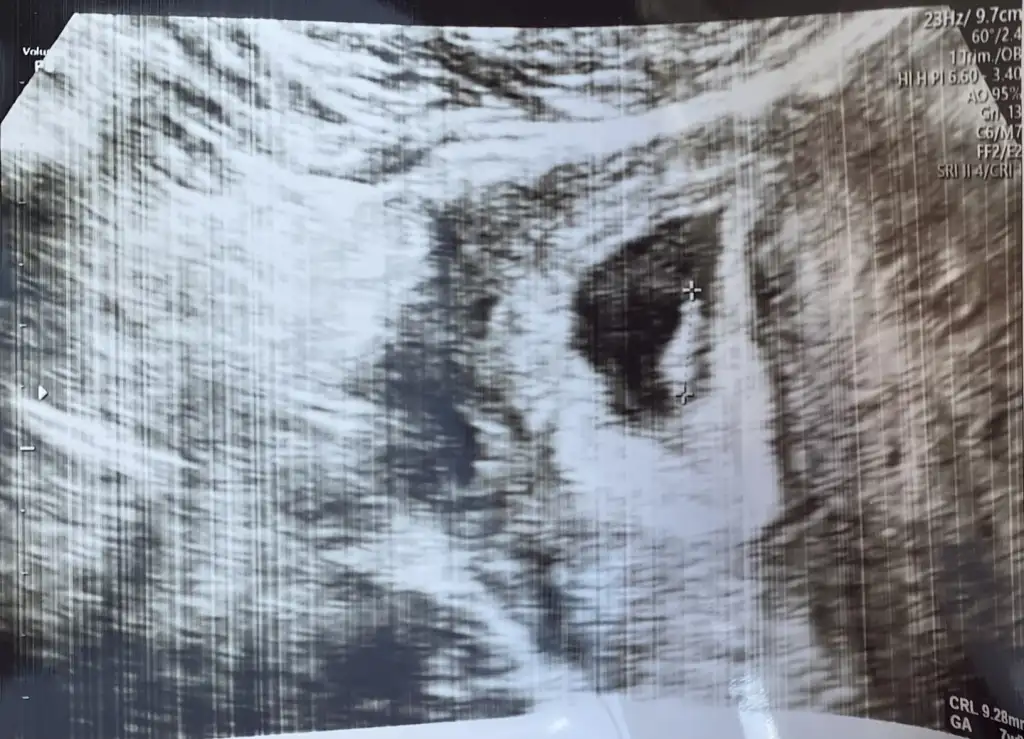

Benim nedir sizce 6+4Sizinde erkek![]()

Ben keseden anlamiyorum kese teorisine de inanmiyorum zatenBenim nedir sizce 6+4

Merak işteBen keseden anlamiyorum kese teorisine de inanmiyorum zaten![]()